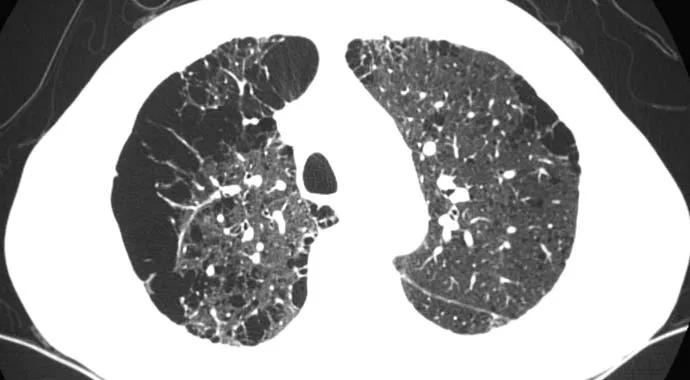

Lung-CT-690×380

To boost early detection and save lives, Medicare now covers annual screenings for patients at greatest risk of developing lung cancer.

CT scans are currently the only approved method for detecting asymptomatic lung cancer in its early stages, when the disease is most treatable. The doses of radiation used in the screening CT are five times lower than the doses used in regular CT scans.

The National Cancer Institute’s National Lung Screening Trial reported in 2011 that annual low-dose CT screenings reduced lung cancer deaths among high-risk patients by 20 percent, with acceptable risks, when performed in high-quality screening programs.